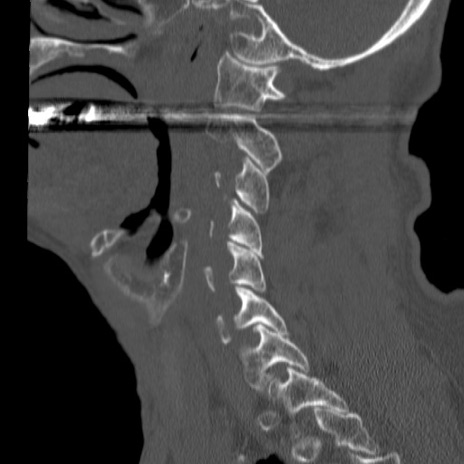

症例46 頚椎CT(矢状断像)

【症例】80歳代男性

【主訴】両側頚部〜上肢のしびれ

【現病歴】昨日、自宅内で転倒、その後より上記症状あり。意識障害なし。

【身体所見】両側上肢のallodynia(熱痛覚過敏)あり。MMTおよびDTRは正確な所見取れず。両上肢の挙上はなんとか可能。

異常所見と診断は?